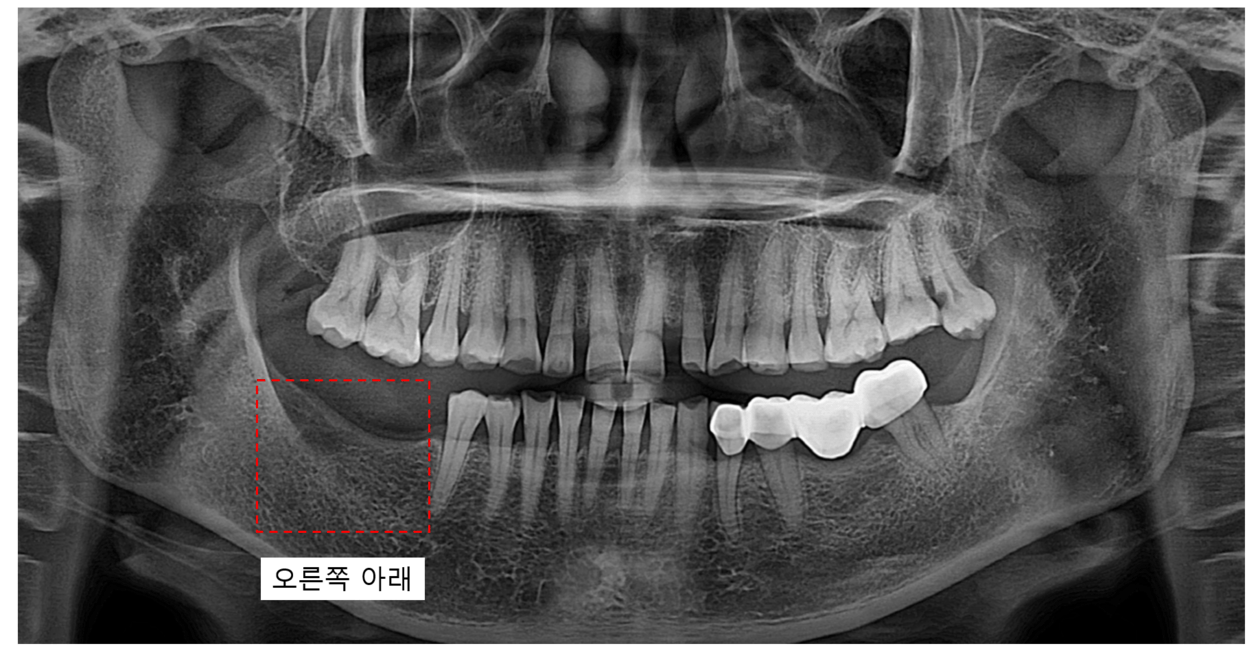

10년 만에 치과 방문, 무서워서 미뤘던 아래 어금니 임플란트

이번 환자분 역시 아래 어금니를 10년 이상 상실한 상태로 내원하셨지만,

CT 정밀 진단 결과 충분히 임플란트 치료가 가능한 상태였습니다.

정확한 임플란트 위치를 사전에 계획하고,

수술 중에도 X-ray로 여러 차례 확인 과정을 거쳐 오차를 최소화합니다.